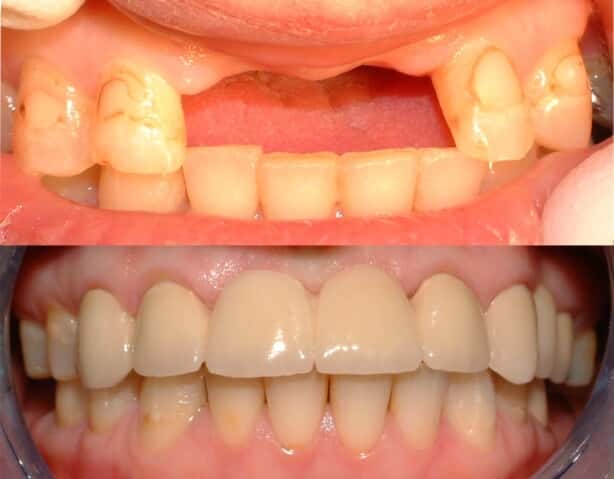

Bridge